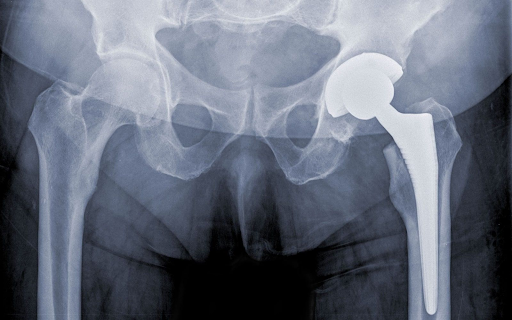

In this procedure, both the damaged ball (femoral head) and the socket (acetabulum) are replaced with artificial implants. It is the most common type of hip replacement.

Artificial components made of metal, ceramic, or high-grade plastic are inserted:

- A new socket is secured in place

- A stem is fitted inside the femur

- A new ball attachment is placed on top